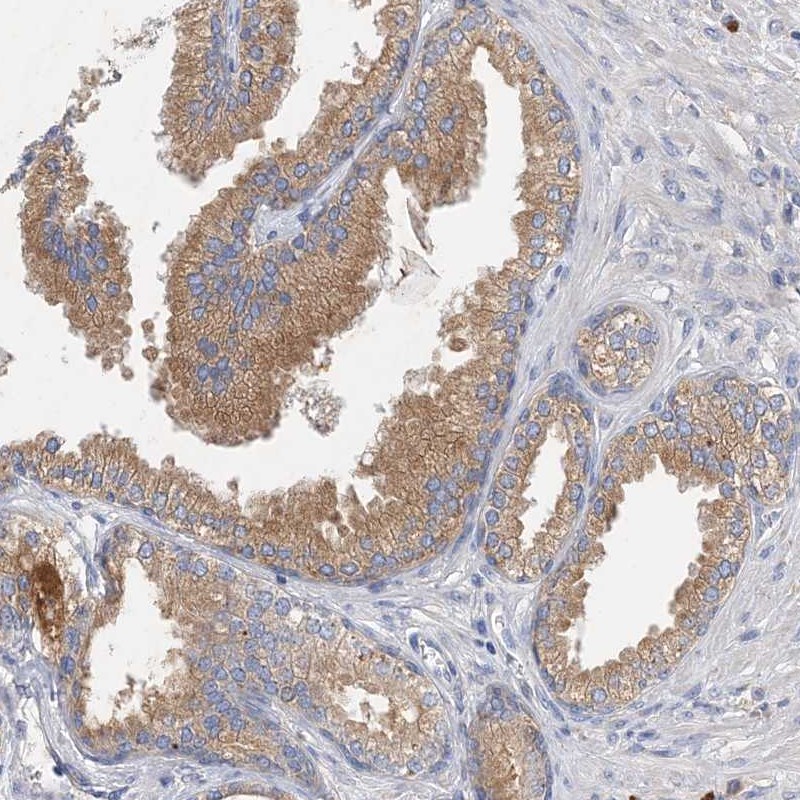

Immunohistochemical staining of human prostate shows moderate cytoplasmic positivity in glandular cells.